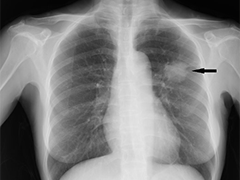

せきが長く続く時は胸のエックス線写真を撮りましょう。肺結核や間質性肺炎、肺がんでは異常陰影が見えることがあります。